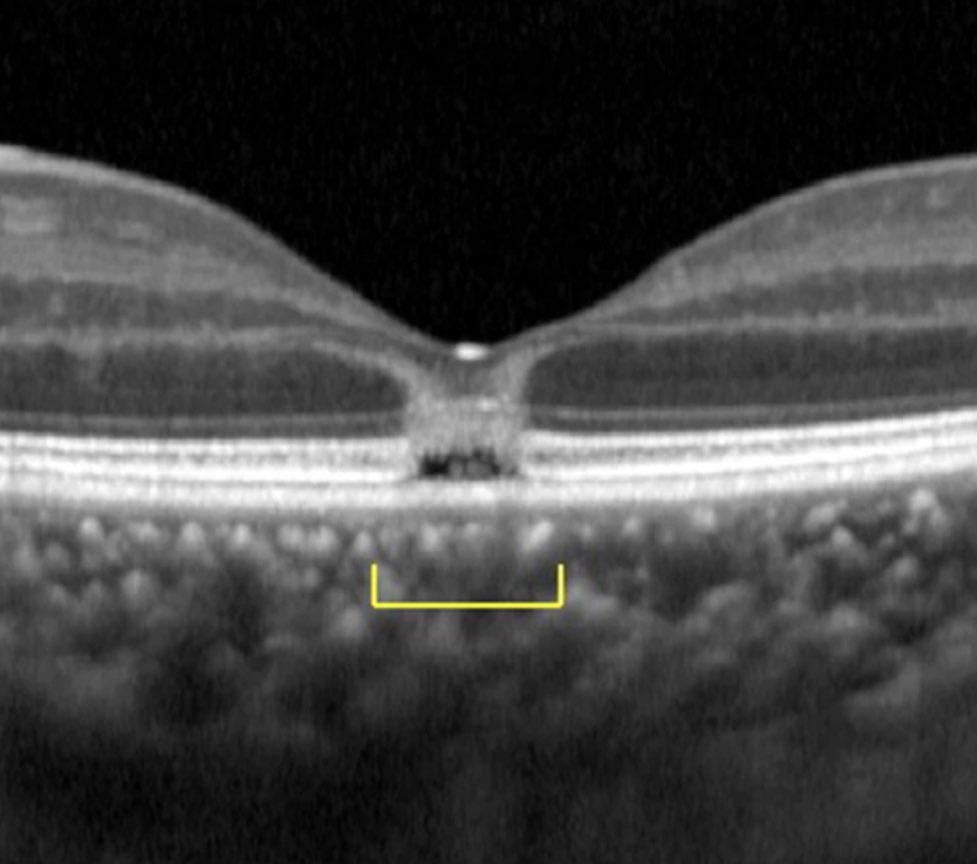

امرأة تصاب بالعمى بسبب النظر للكسوف (مع استخدامها نظارة خاصة بالكسوف!)

والسبب؟ النظارة مغشوشة ولاتحمي من اشعة الشمس

النصيحة تجنب النظر للشمس وقت الكسوف حتى مع نظارة الحماية، الضرر بالشبكية غير قابل للعلاج!